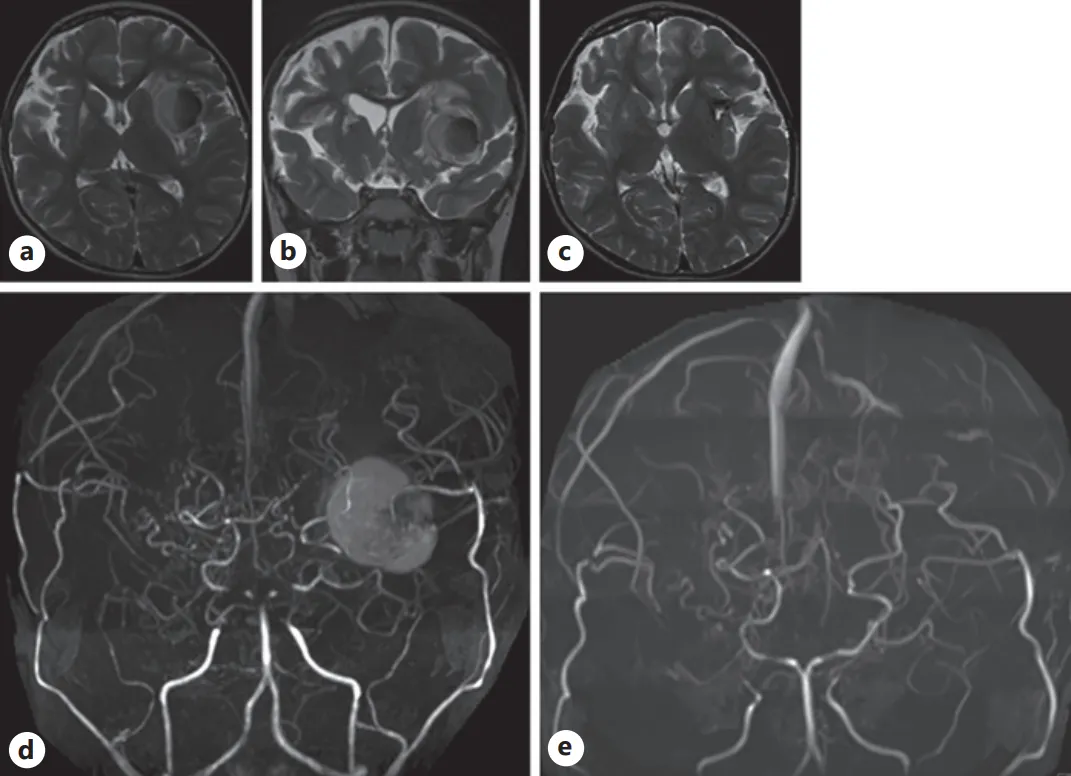

随访轴位(a)与冠状位(b)T2加权磁共振成像(MRI)图像:可见左侧岛叶病灶扩大至原先的两倍以上,周围伴有水肿组织;

(c)术后T2加权MRI显示,原异常病灶已被手术疤痕组织取代;术前(d)与术后(e)磁共振血管造影(MRA):术前MRA上的较大病灶在术后影像中已完全消失。